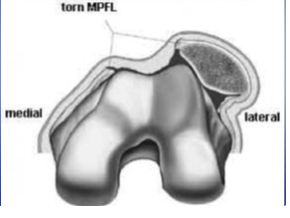

Why are most patellar dislocations lateral?

The medial patellofemoral ligament (Retinaculum) is more likely to tear than the lateral patellofemoral ligament (Retinaculum)